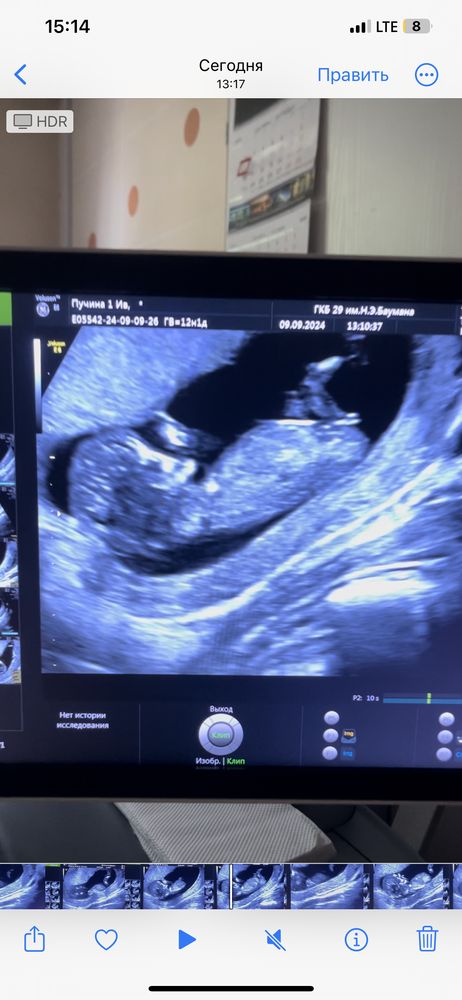

Девчонки, угадаем пол по узи?

Если то, что я вижу - половой бугорок, а не что-то другое, то похоже на девчонку) Изображение

Если я правильно вижу половой бугорок это девочка😻